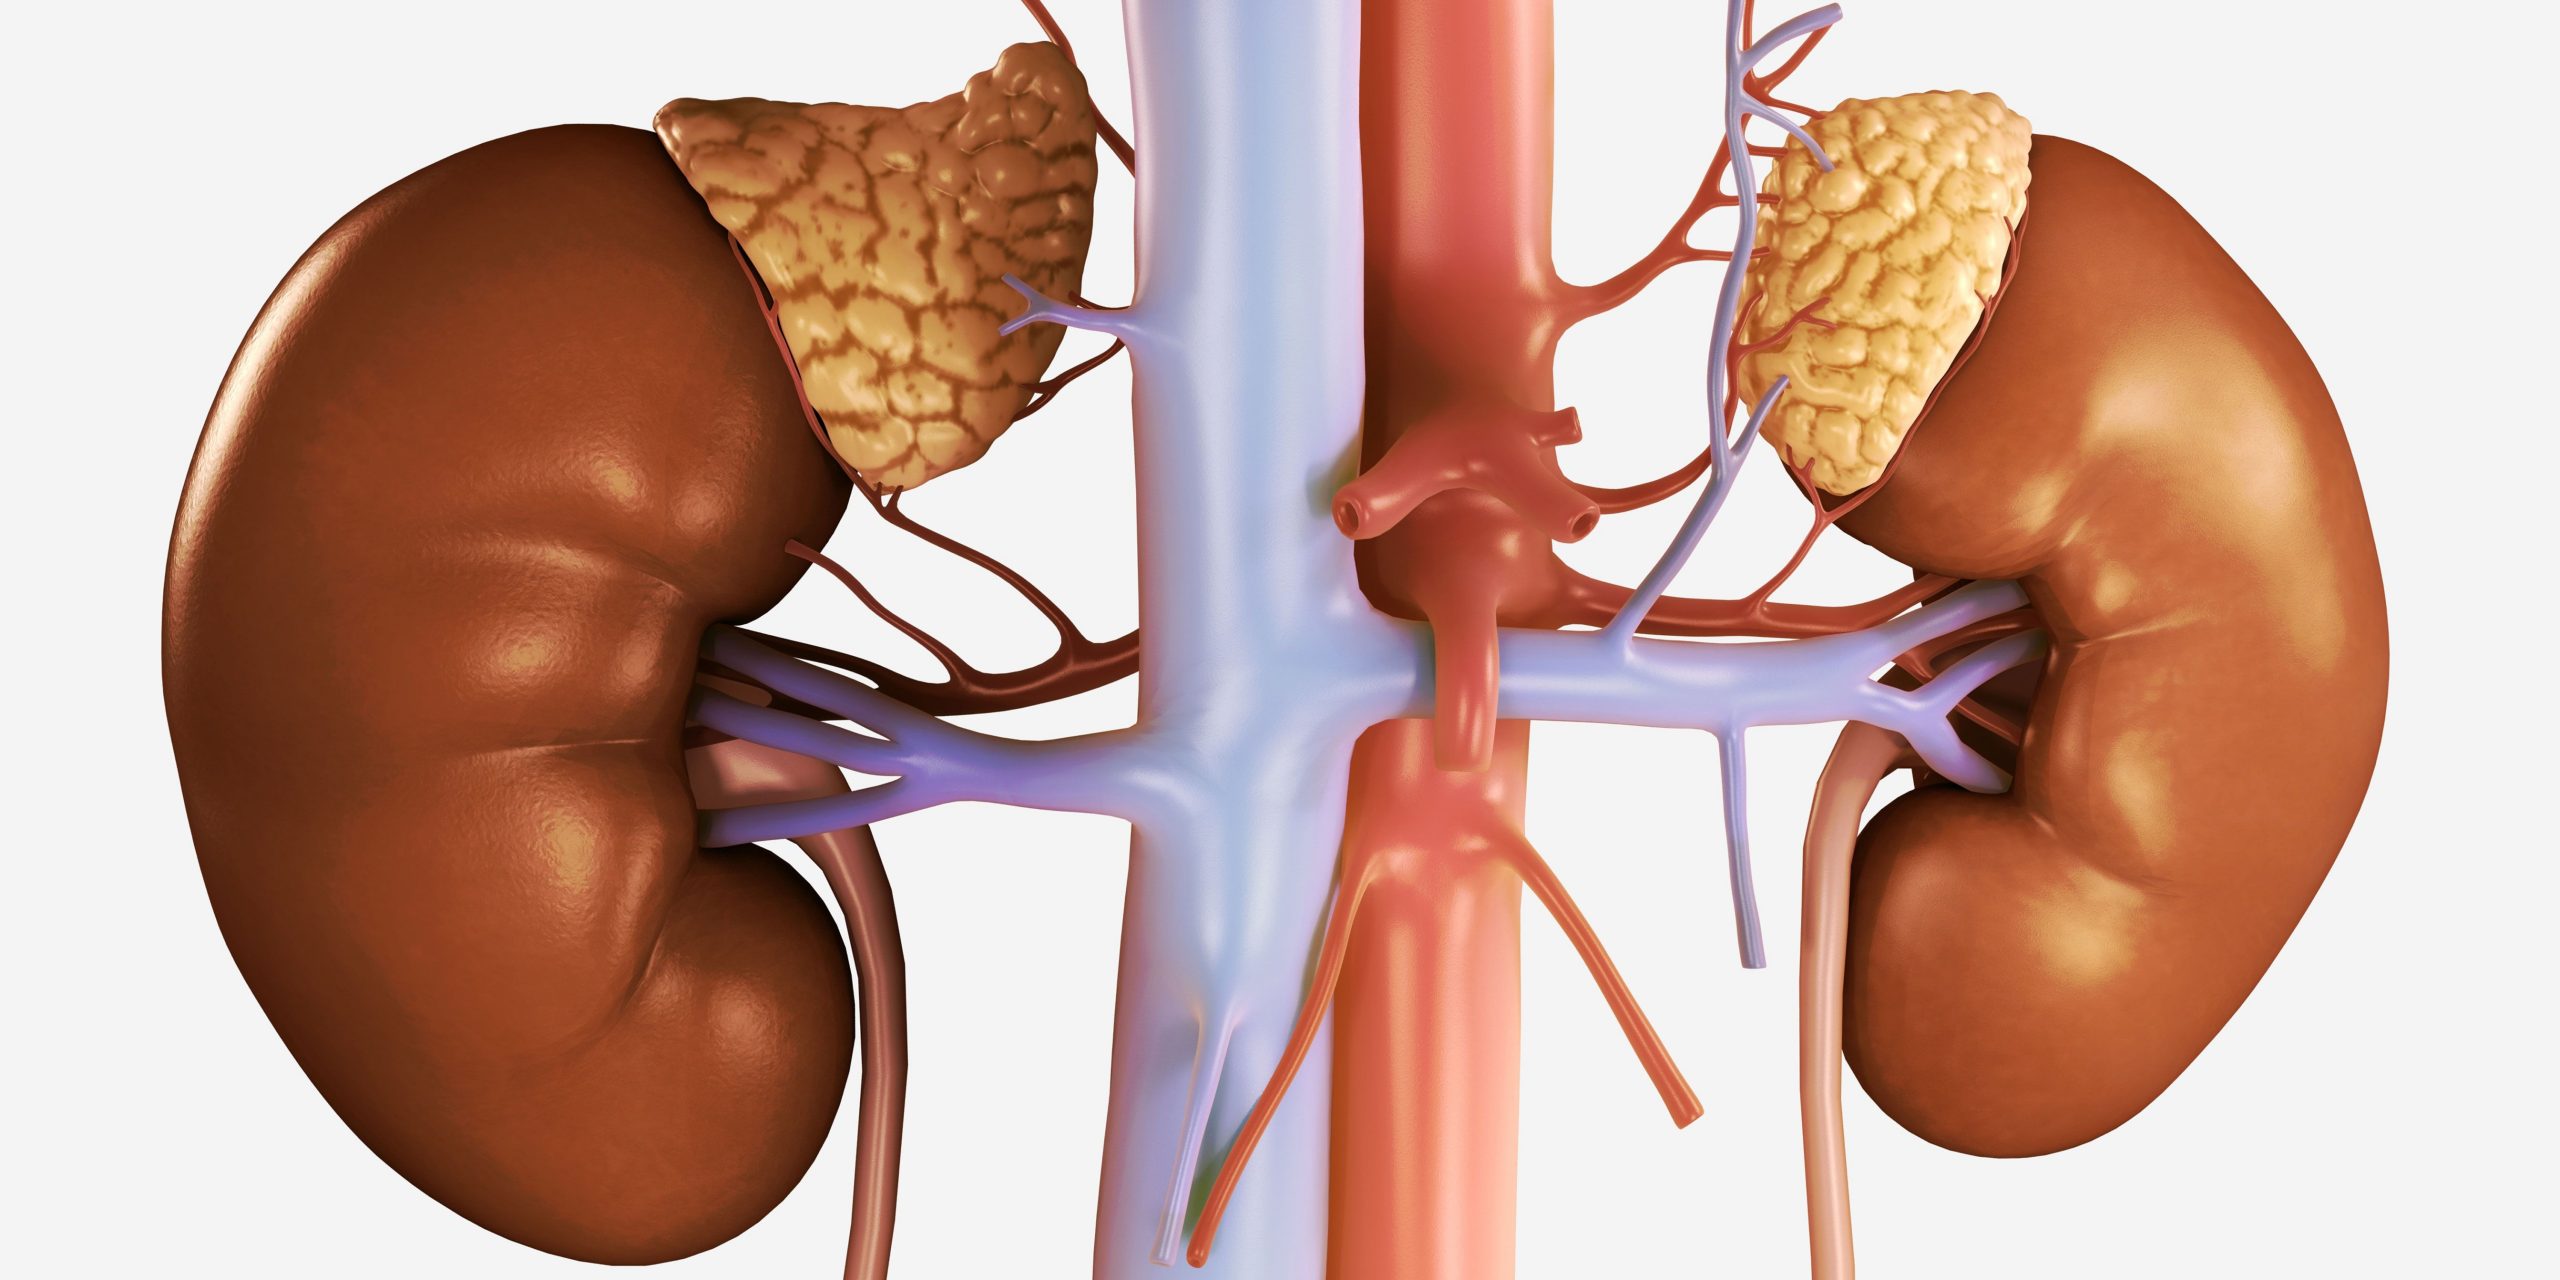

وظایف کلیه ها در بدن. و دخالت این چهار مایع را در کلیه حالات بدنی. شکل زیر عکس واقعی کلیه انسان را نشان می دهد. اگر عملکرد آن ها کم شود نیاز به دیالیز پیدا می کنند.

کلسیم و فسفر که برای تشکلی استخوان لازمند کمک می کنند مواد. کلیه ها با تولید ادارد در دفع مواد زاید تعادل الکترولیتی تنظیم هورمونی تنظیم فشار خون و هوموستازگلوکز نقش دارند. آناتومی کلیه انسان در بدن انسان به این شکل است که کلیه ها دو عضو لوبیایی شکل در دستگاه ادراری بوده و به دفع مواد زائد به صورت ادرار کمک می کنند. یکی از مهم ترین وظایفی که کلیه ها در بدن بر عهده دارند پاک کردن و تصفیه خون از زباله هاست.